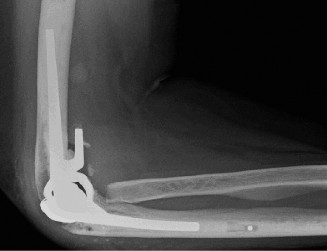

The correct answer is (C). Core decompression via insertion of pins into the area affected by AVN is thought to improve symptoms in patients with Ficat stage I or II by reducing bone marrow pressure and encouraging new vasculature to form. Patients are managed postoperatively in a sling for a few days and can perform shoulder range of motion as tolerated. Choice A would be more appropriate in a more advanced stage of AVN and/or if conservative treatment and core decompression have failed to relieve pain. Choices B and D are incorrect as they would be reserved for the elderly patient with advanced AVN characterized by concurrent osteoarthritic changes, with or without rotator cuff function. Objectives: Did you learn...? Understand the etiology of osteonecrosis of the humeral head? Recognize the clinical presentation of osteonecrosis of the humeral head? Manage a patient with osteonecrosis of the humeral head? CASE 20 Dr. Anna Cohen-Rosenblum A 72-year-old, right-hand-dominant male with a history of type 2 diabetes, hypertension, and coronary artery disease presents to clinic for a second opinion regarding worsening left shoulder pain 8 months after undergoing a left total shoulder arthroplasty. He had an uncomplicated procedure and has had no major postoperative complications thus far; however, he has never been completely pain free since his procedure. He denies any recent trauma, fevers, chills, or drainage from the incision site. On examination, the incision sites are clean, dry, and intact, and he has mild tenderness to palpation diffusely over the left shoulder as well as decreased range of motion. Imaging is shown in Figure 2–55.

Figure 2–55

What is the most appropriate next step in his management?

The correct answer is (C). This patient’s story of acutely worsening pain without known trauma and with a history of orthopaedic implants is suspicious for infection. Risk factors for infection include rheumatoid arthritis, diabetes mellitus, systemic lupus erythematosus, malignancy, immunosuppression, etc. The first step in this diagnosis would be CT arthrogram of the shoulder to evaluate for loosening as sign of infection. A is incorrect as, although infection is on the differential, it has not yet definitively been diagnosed and therefore an immediate irrigation and debridement would not be indicated. MRI (Choice B) might be helpful in identifying a joint effusion or bony edema/signal intensity but would not provide as useful information as synovial fluid would at this point. Choice D is incorrect because the patient must be worked up for infection before deciding on conservative

CT arthrograms of the patient’s left shoulder are shown in Figure 2–56. CRP is <3, ESR 45. The patient continues to have pain, so you decide to perform arthroscopic biopsy to obtain tissue cultures. Frozen sections show <5 PMNs per hpf, and Gram stains are all negative.

Figure 2–56

What is the next step in management of this patient?

The correct answer is (B). Figure shows contrast under the glenoid component. Given the patient’s normal inflammatory markers and frozen sections combined with continued pain and loosening on CT, infection with P. acnes(an organism that is very difficult to isolate) should be investigated by holding any cultures for at least 2 weeks to see if it will eventually grow. Chocolate agar (Choice C) is mainly used for growing species such as H. influenzae and Neisseria meningitidis not P. acnes. A is incorrect since the patient’s cell count and frozen sections are clearly abnormal, therefore referral to pain clinic would not be appropriate. However, Choice D would be too aggressive an approach given that no organisms have been isolated, frozen sections show <5 PMNs per hpf, and the patient has relatively normal inflammatory markers.